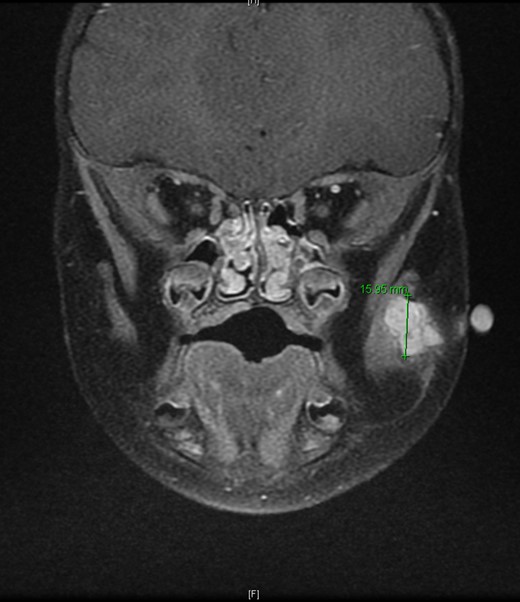

T2-weighted MRI 2 months later revealed a 14.5 mm × 14.1 mm × 15.95 mm mass partially involving the masseter muscle with no internal vascular flow voids.

An 11-month-old male with a history of nasolacrimal duct stenosis and 4 mm thyroglossal duct cyst presented for evaluation of left facial swelling for 9 months. Approximately 6 months prior to admission, a mass was identified on the left cheek which had progressively increased in size over the past 2 months. The patient also had intermittent fevers the week prior to admission but was otherwise healthy. Baseline labs, including platelets, were within normal limits. On exam, he was found to have a firm, mobile, non-tender mass just inferior to the left zygomatic arch. Ultrasound revealed a vascularized solid lesion measuring 12 mm × 15 mm × 16 mm limited to the superficial soft tissues. MRI showed a multi-lobular mass with increased T2 signal centered within the left masseter and infiltrating signal in surrounding subcutaneous tissue (Fig. 1). The patient subsequently underwent ultrasound-guided core biopsy. The initial pathological diagnosis was consistent with TA, showing fibrovascular tissue containing compact nests of variably sized and ill-defined vascular channels. Immunohistochemistry staining showed the endothelial cells to be diffusively reactive for CD34 and CD31, partially reactive for D2-40, and negative for GLUT-1. However, upon further review, KHE was favored given the solid and infiltrative components on MRI, normal overlying skin on exam, and location of the lesion within subcutaneous fat. Accordingly, low-dose daily aspirin was prescribed prophylactically to prevent KMP. An MRI 2 months later, along with serial ultrasound images in the ensuing 26 months, showed no further growth (Fig. 2). His parents noted intermittent painless changes in size that did not seem to be related to any stimulus and returned to baseline size within hours. Surgical intervention at 3 years old is anticipated.